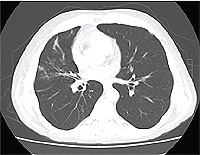

A 42 year-old white male, with ALL, 8 months post-allogeneic unrelated donor BMT with a past history of Graft versus host disease, was admitted with dyspnea and cough with clear color sputum. Ten days prior to current admission he was treated for right middle lobe infiltrate with change of voriconazole from prophylactic to full treatment dose, with the addition of gatifloxacin, and continuation of famciclovir and bactrim at prophylactic doses.

Physical examination showed blood pressure 100/74, pulse rate 127, respiratory rate 22, and temperature 98.7, pulse oximetry 98% on room air. Right eye dryness was observed. Lungs were clear to auscultation. Heart sounds regular with tachycardia. The abdomen was diffusely tender without guarding or rebound. WBC was 22K, Hct, 25, and platelet count 30K. BUN/creatinine wee 39 and 1.8. The CT scan is shown below

The patient was started on vancomycin, imipenem, and changed from voriconazole to Abelcet, to cover for suspected invasive pulmonary Aspergillosis. Also started on steroids and tacrolimus for presumed exacerbation of GVHD. Respiratory failure complicated hospital course requiring endotracheal intubation and mechanical ventilation. The patient developed hemoptysis with bronchoalveolar lavage significant for alveolar hemorrhage. The patient subsequently developed right side paralysis, with head CT showing left frontal infarct and right occipital punctuate hemorrhages. Peripheral macular lesions consistent with infectious hematogenous spread was also noticed. After One week in ICU, patient's family decided to change status to comfort care only and the patient died.

Blood cultures were positive for fungi in hyphae form (Figure-3) and fungal culture from BAL were positive for Scedosporium prolificans.

Diagnosis

Disseminated Scedosporium prolificans infection.